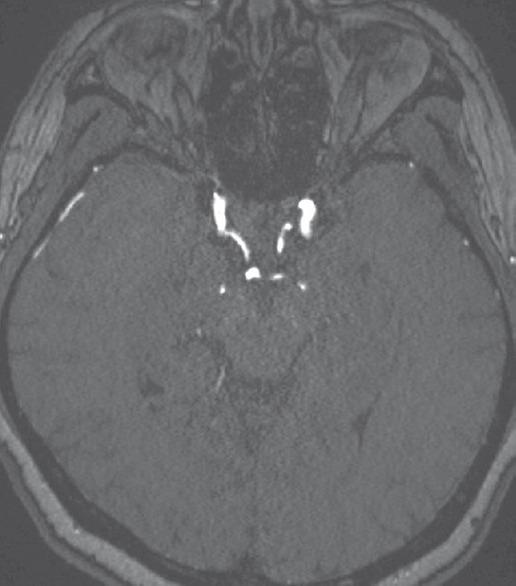

Internal carotid artery (ICA) blister aneurysms are rare and challenging to successfully treat, using contemporary surgical or endovascular approaches, without partial or complete compromise of the parent vessel. We describe the use of a resheathable flow diverter, the Pipeline Flex Embolization Device (PFED) to perform stent-assisted coiling of a ruptured supraclinoid ICA blister aneurysm in a 56-year-old female who presented with a high-grade subarachnoid hemorrhage (SAH). The first PFED was deployed across the aneurysm neck to jail a microcatheter within the aneurysm dome, and then, two small coils were delivered into the aneurysm. After removing the coiling microcatheter, the second PFED was telescoped into the first PFED. There were no postprocedural complications, and follow-up magnetic resonance angiography 15 months after embolization showed complete aneurysm obliteration. Flow-diverting stent-assisted coiling should be considered as a reconstructive, vessel-preserving, endovascular treatment option for appropriately selected patients with ruptured ICA blister aneurysms. However, future studies are necessary to assess the periprocedural safety in the setting of acute SAH.

颈内动脉(ICA)泡状动脉瘤较为罕见,采用当代手术或血管内治疗方法成功治疗且不部分或完全损伤载瘤血管具有挑战性。我们描述了使用一种可重新鞘内放置的血流导向装置——Pipeline Flex栓塞装置(PFED),对一名56岁出现高级别蛛网膜下腔出血(SAH)的女性患者的破裂鞍上ICA泡状动脉瘤进行支架辅助弹簧圈栓塞治疗。首先将第一个PFED部署在动脉瘤颈部,将微导管置于动脉瘤腔内,然后将两个小弹簧圈送入动脉瘤。取出弹簧圈栓塞微导管后,将第二个PFED套入第一个PFED。术后无并发症,栓塞后15个月的随访磁共振血管造影显示动脉瘤完全闭塞。对于适当选择的破裂ICA泡状动脉瘤患者,血流导向支架辅助弹簧圈栓塞应被视为一种重建性、保留血管的血管内治疗选择。然而,未来有必要开展研究以评估急性SAH情况下围手术期的安全性。